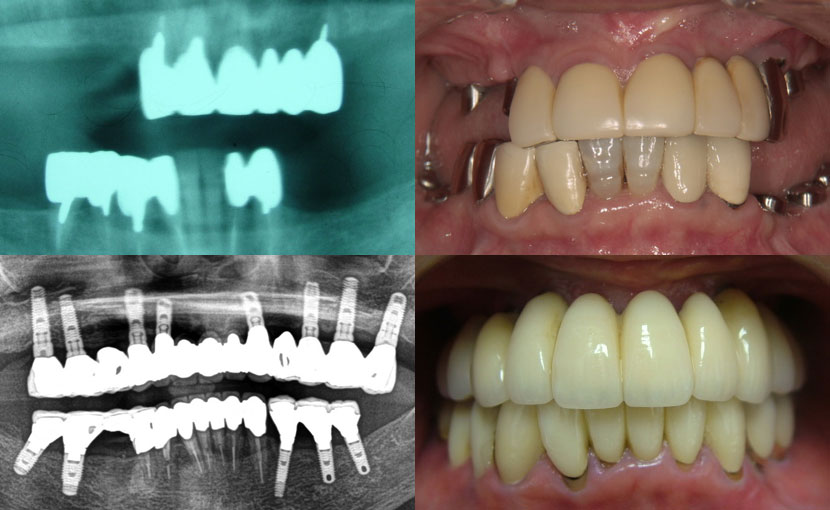

術前

• 初診:2019年、40代男性、非喫煙者、アレルギー体質(花粉症)

• 矯正診断:3級骨格性の反対咬合

• 治療方針:以前に治療したほぼ全ての歯の再治療(虫歯治療、歯内療法、歯周処置)、矯正用インプラントを用いたワイヤー矯正、修復処置(被せ物)、保定(上マウスピース、下ワイヤー)、メンテナンス